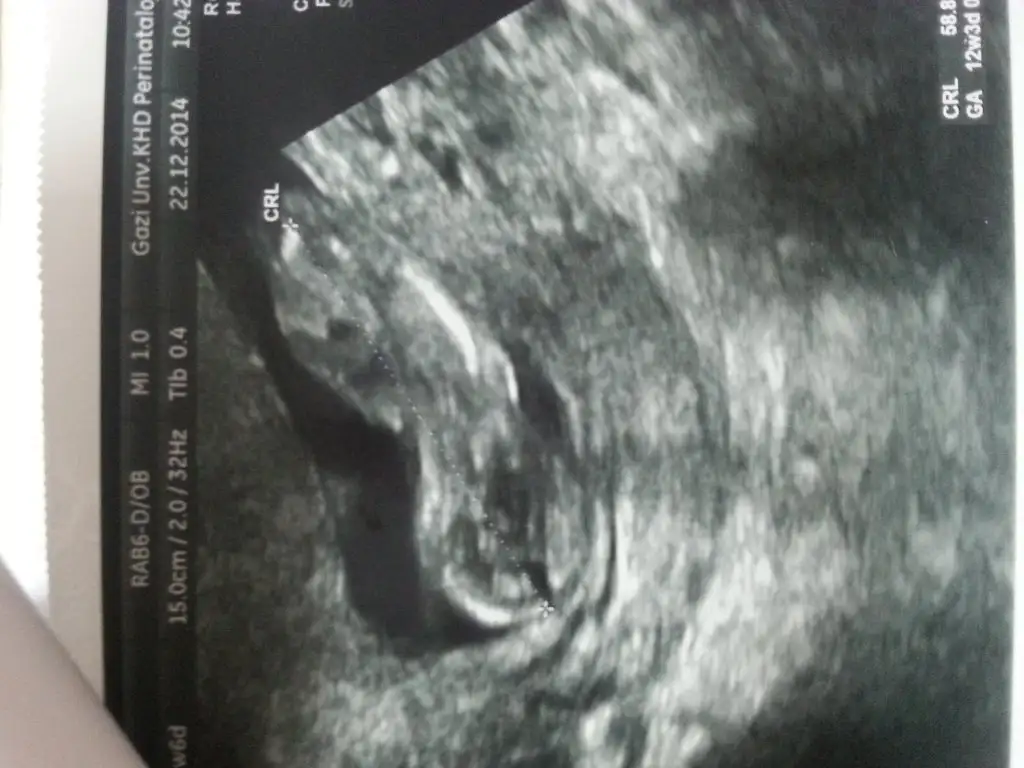

Erkek diyorlar bende eğer göbek kordonu değilse gördüğüm erkek diye dusunuyom bi arkadaş var tecrübeli o yorum yaparsa onuda yazacam orkidem yani okisi

Bu resimde tam 14 haftalık

Anladım canım cok sagol beni mutlu ettin ilginle :) ıkı ayrı doktor bana erkek tahmininde bulundu ama 3 buçuk olunca kesinleşır dedim ama gostermiyo dedi